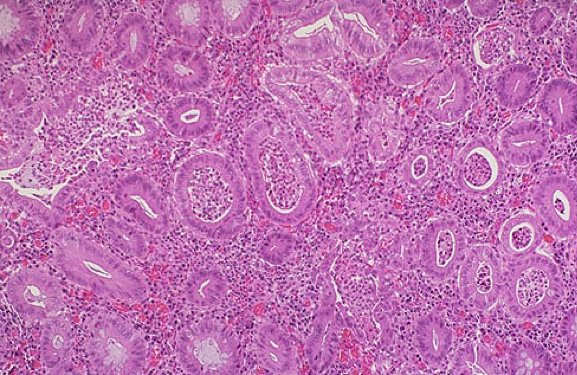

What is going on in these 2 images?

What do you see here?